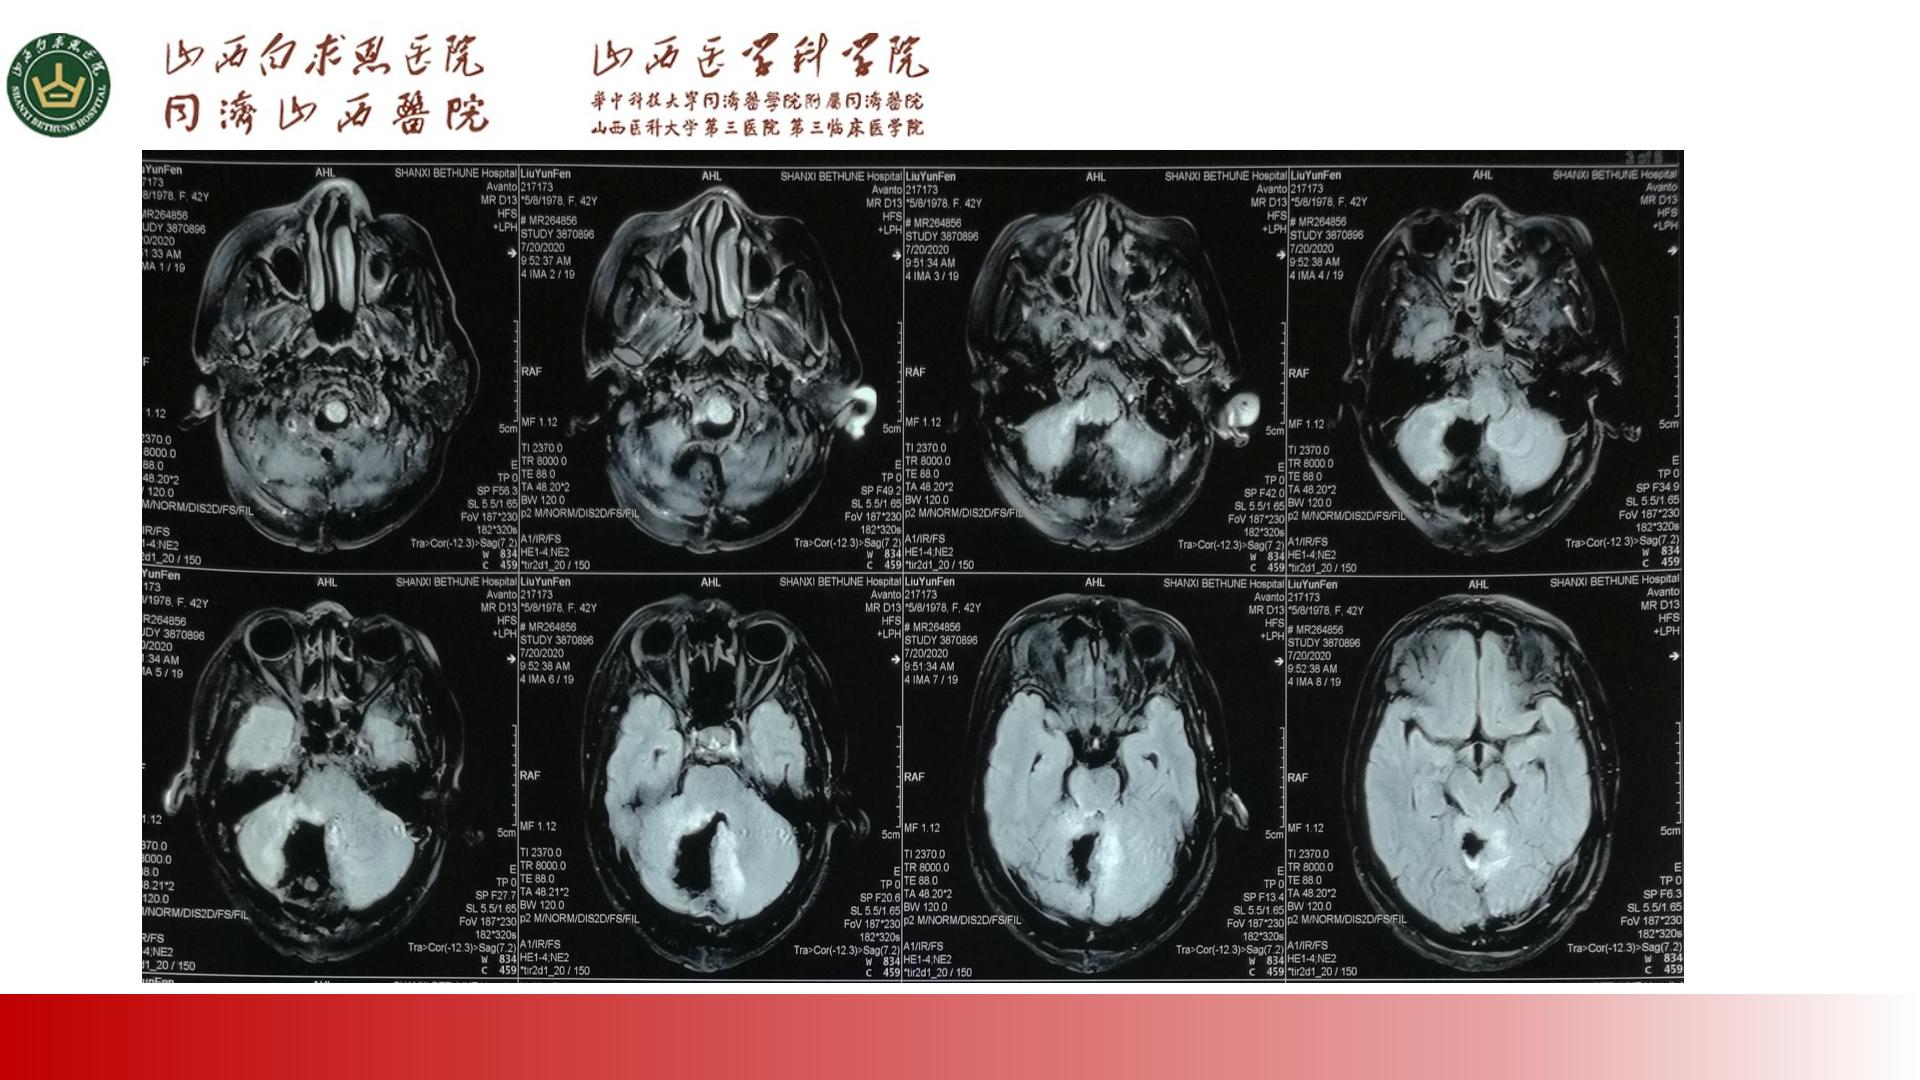

PPT:两例小脑节细胞胶质瘤治疗体会